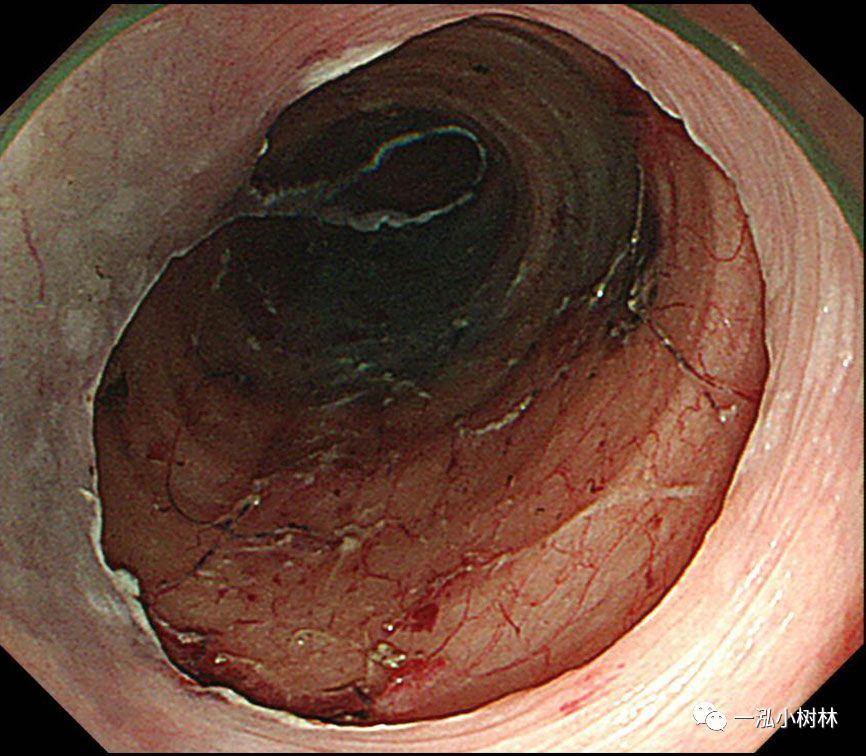

图10 牵引线从嘴中拉出以产生牵引力

图11 黏膜整块切除